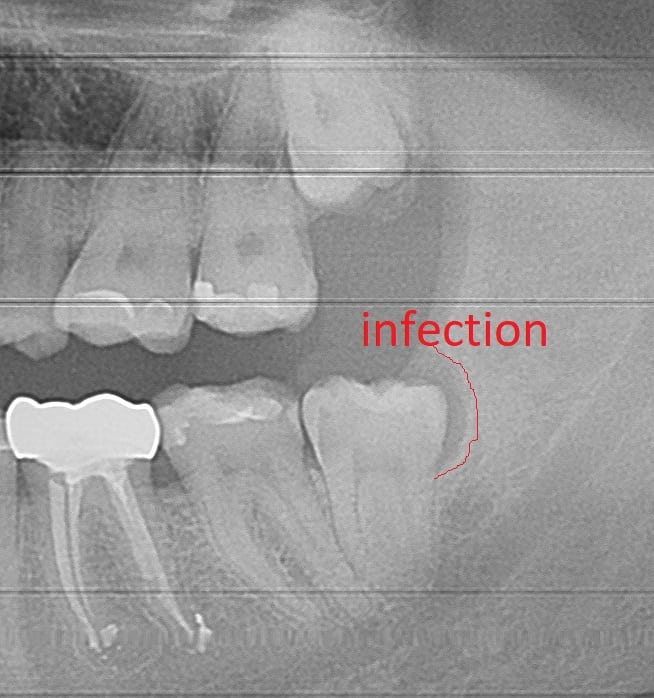

A common dental emergency frequently seen in dental offices is pain caused by a wisdom tooth. Very often gum infection around the wisdom tooth, called pericoronitis is the source for discomfort. Usually, this infection requires the removal of the offending wisdom tooth for the pain to be resolved.

Wisdom tooth infection, also called Pericoronitis, is the most common cause for wisdom tooth extractions. It’s very difficult to keep wisdom teeth clean because they’re often covered by gum tissue. Over time, the food particles that are not cleaned under the gum will become a source for bacterial growth. This infection will cause swelling and discomfort for the patient. The most effective treatment is wisdom tooth extraction.

Antibiotics often take several days (2-3 days) to be effective. Patients with wisdom tooth pain will usually benefit the most with wisdom tooth extraction combined with a course of antibiotics. When patients just take antibiotics without the removal of the infected wisdom tooth, the infection will usually return within a few months.